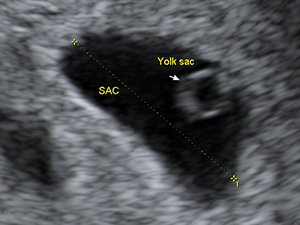

早孕期

懷孕6週的胎囊與卵黃囊